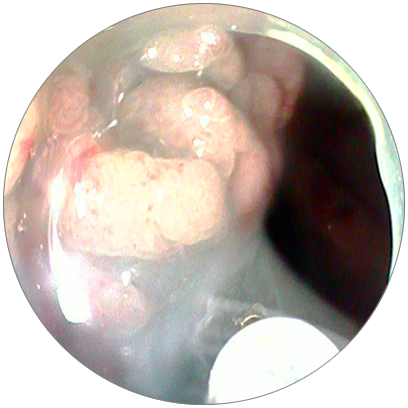

進(jìn)鏡到

肛側(cè)距肛門約7cm直腸處

可見一個(gè)大小約2*4cm的

側(cè)向發(fā)育型腫瘤

表面凹凸不平

呈結(jié)節(jié)狀